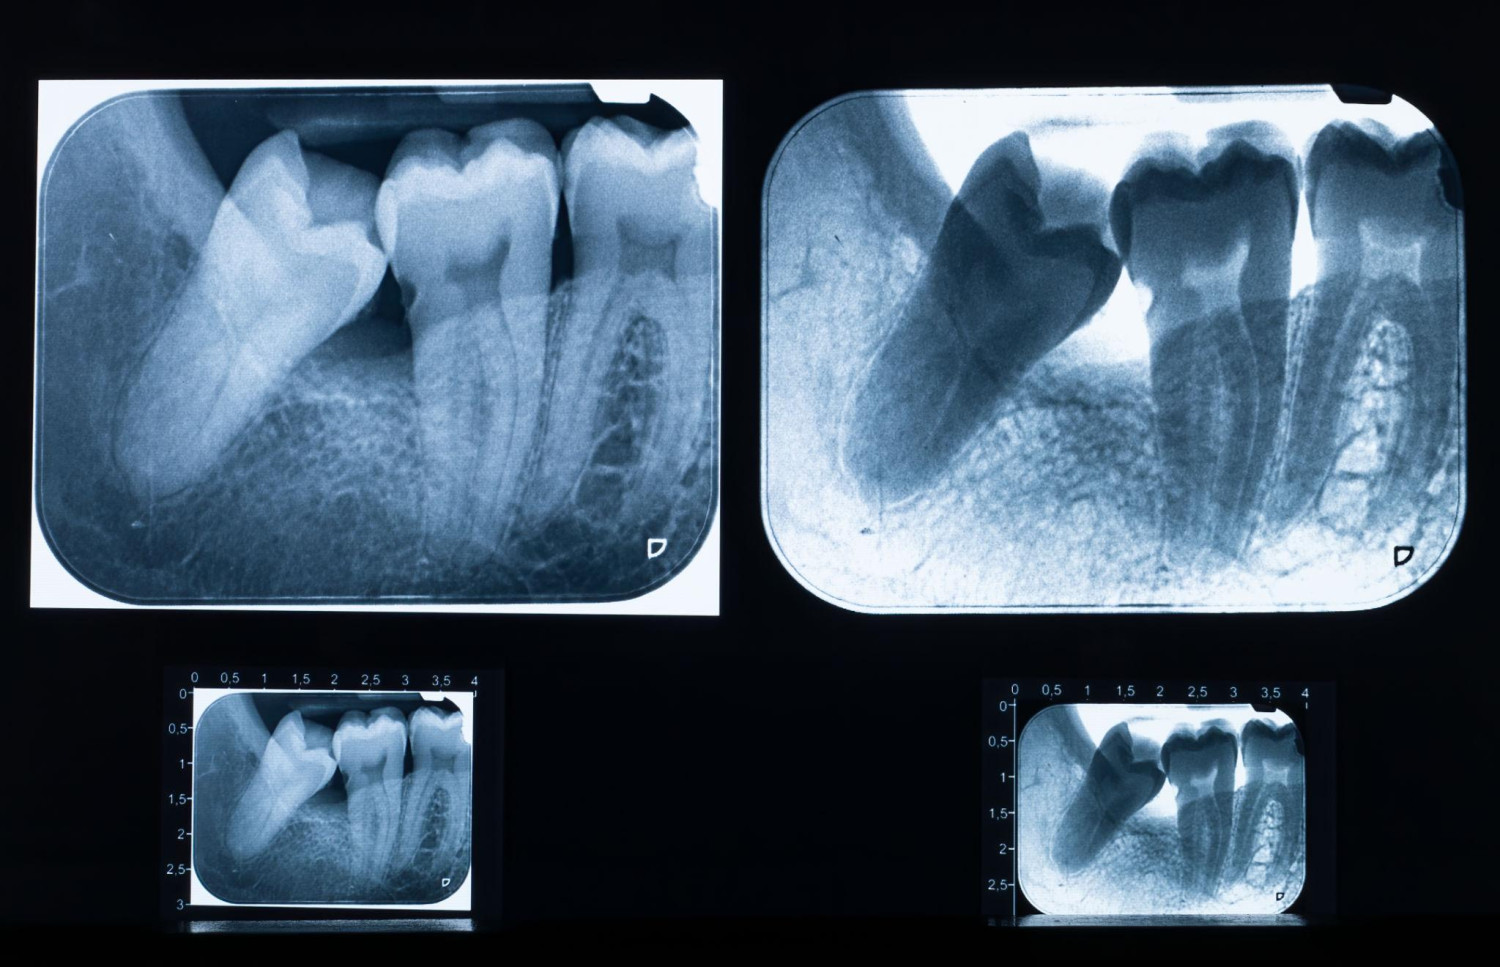

• Thăm khám và chụp phim trước khi nhổ

• Đánh giá vị trí răng khôn chính xác